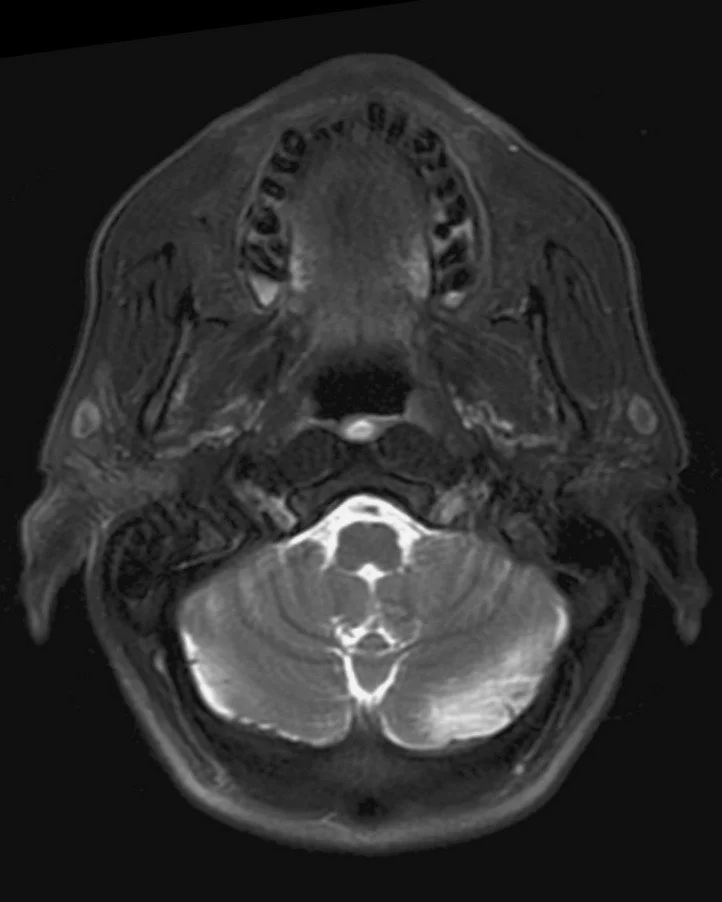

• Convoluted cerebriform pattern (alternating stripes of high and low intensity on MR)

• T1: Isointense to muscle, heterogenous enhancement

• T2: hyperintense to muscle